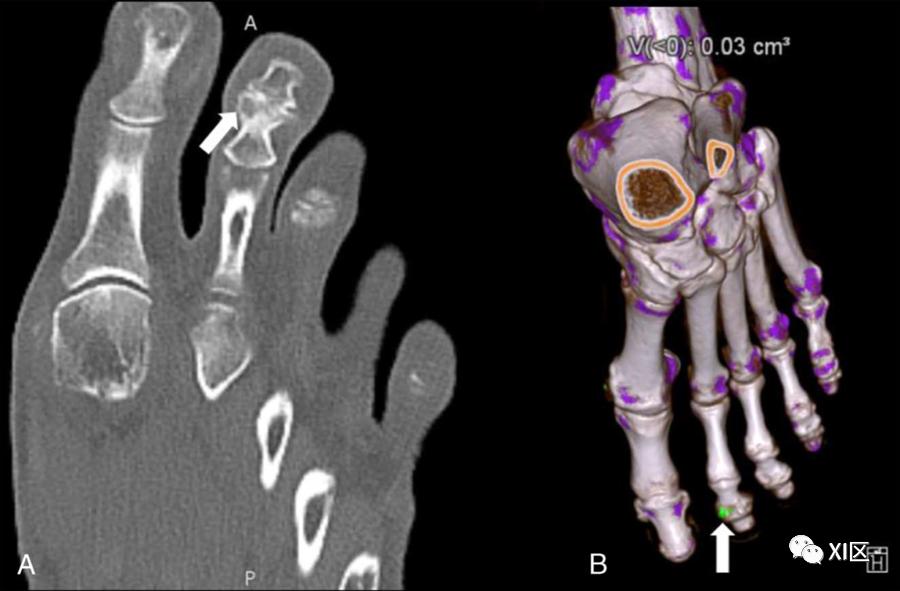

DECT的一个有趣的用途是使用多平面和3D材料分解重建来诊断痛风,类似于区分尿酸肾结石和其他肾结石成分(图6)。最近的一项荟萃分析显示,在超过2年的病程中,使用DECT检测痛风的敏感性和特异性高于超声。

图6:一名65岁多关节疼痛患者的DECT,血清尿酸持续升高。A、 痛风关节病特征的第二远端指间关节侵蚀的显示(箭头)。B、 DECT采集的材料分解3D重建,在该采集上,在同一接头上以绿色显示尿酸钠沉积物(箭头)。在一项模拟研究中,最近区分晶体沉积类型的努力成功地将尿酸钠沉积(痛风中普遍存在)与焦磷酸钙(假性痛风中普遍出现)或羟基磷灰石钙沉积区分开来,对不同DECT分解方法的探索证明了3D虚拟单色采集在受试者足部和踝关节的体模对照研究中对尿酸钠沉积物的定量和检测中的实用性。